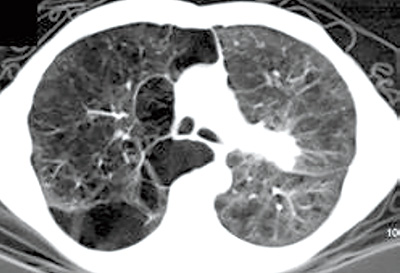

ICI治疗COPD合并晚期NSCLC时 CT可见的肺气肿或为潜在的预后标志

西班牙研究者Di Frisco等报告,在免疫检查点抑制剂(ICI)治疗的、慢性阻塞性肺疾病(COPD)合并非小细胞肺癌(NSCLC)患者中,胸部CT上视觉发现的肺气肿可能是潜在的预后标志。后续研究有必要进一步验证这些发现。(J Thorac Oncol. 2025年10月21日在线版)

COPD和肺气肿是肺癌发生的独立风险因素,并且在ICI治疗的NSCLC患者与更长的总生存期(OS)独立相关。然而,它们共同对预后的影响仍不清楚。

为了评估肺气肿在免疫治疗的COPD合并晚期NSCLC患者中的预后作用,该项研究纳入了2013~2024年ICI单药一线或二线治疗的、COPD(经肺功能测定)合并晚期NSCLC患者,根据胸部CT视觉发现的肺气肿将患者进行分类。

结果显示,研究共包括111例COPD合并肺癌的患者,其中77例合并肺气肿。与无肺气肿患者相比,COPD合并肺气肿患者的OS显著延长(17.3个月 vs. 8.5个月,P=0.008),无进展生存期(PFS)也呈临界的改善趋势(3.3个月 vs. 2.4个月,P=0.641)。多因素分析显示,肺气肿仍然是更长OS的独立因素(HR=0.49,95%CI 0.30~0.81)。不良事件发生率在不同肺气肿状态之间无显著差异(P=0.455)。